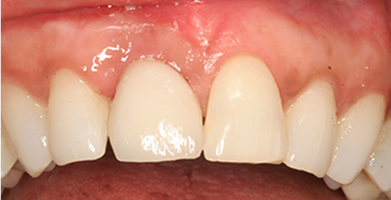

Multiple Implants

Used to restore several missing teeth or support a full arch restoration.

BEFORE

AFTER